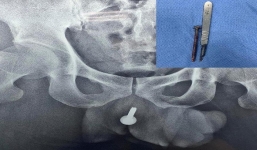

Nhậu say, 'thần cồn' bị bạn cùng bàn nhét chiếc vít dài 6cm vào đường tiểu